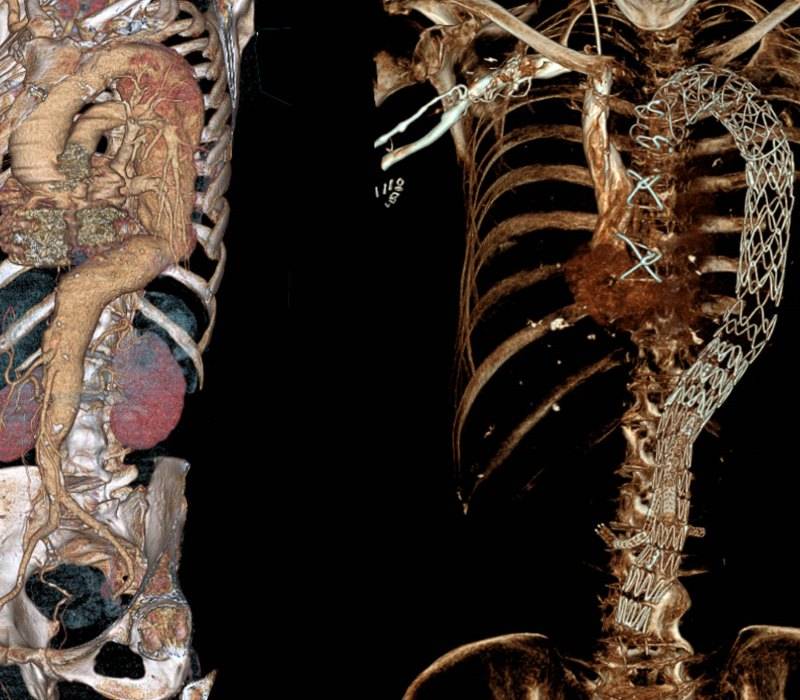

Sustitución de una aorta completa, del corazón a las piernas

Mediante dos intervenciones consecutivas se ha reemplazado una aorta que sufría aneurisma en toda su extensión

Si ya de por sí un aneurisma de aorta es extremadamente grave, ya que se puede producir la rotura de la arteria debido a la dilatación existente en las paredes, cuando además este aneurisma afecta a toda su extensión el caso se complica aún...